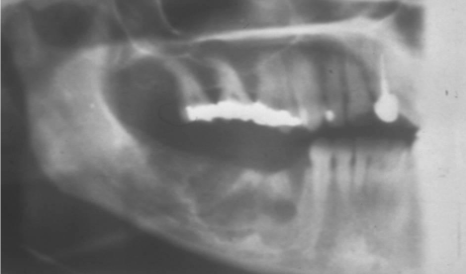

how would you describe this radiographic lesion?

an apical well-defined radiopaque lesion